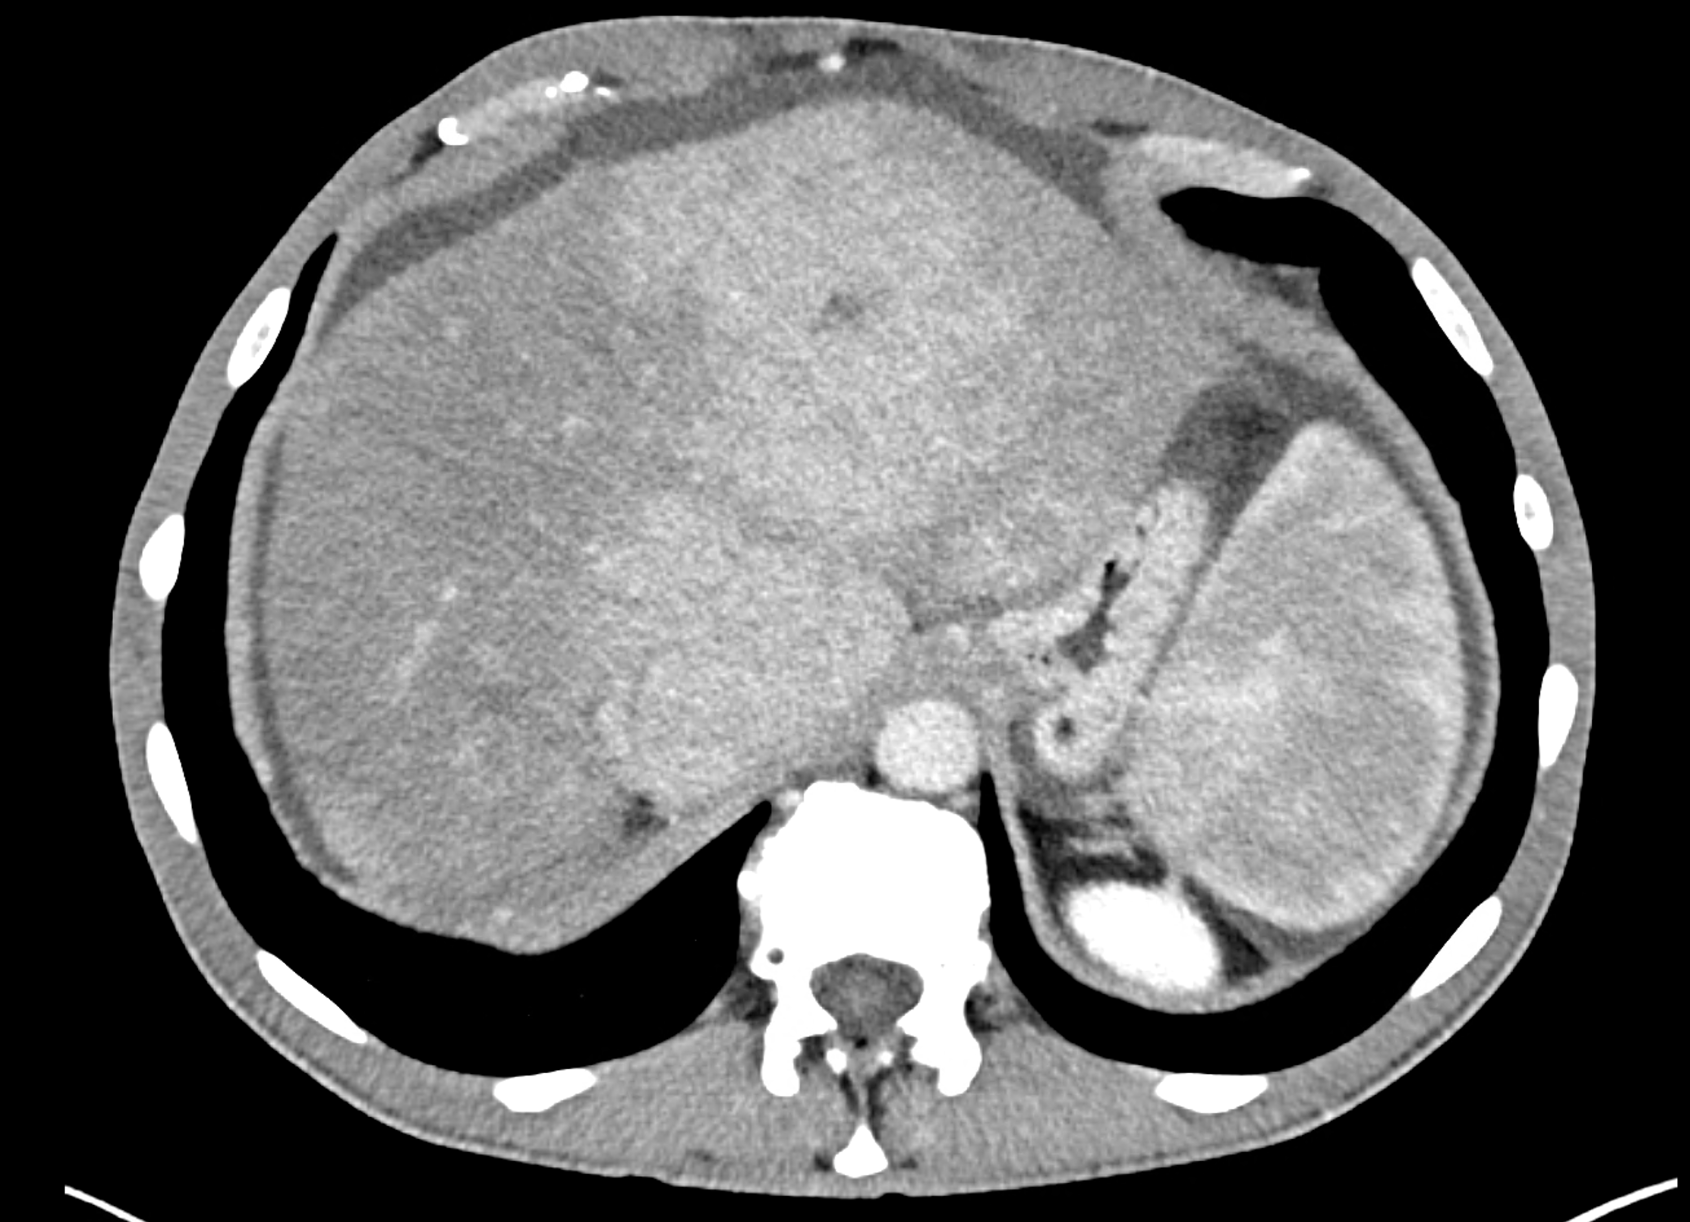

In CT images, BCS manifests as non-homogeneous enhancement of liver tissue in the arterial and especially in the portal phase, although in the portal phase may be increased, especially in the caudate lobe and left lobe, which are often hypertrophic (the hypertrophy and the enhancement is caused due to the possibility of the venous drainage directly into the inferior vena cava through the direct caudate veins), in contrast to the reduction in the right lobe. The portal vein is free, whereas even in the late phase, the hepatic veins and their contrast filling are not visible. Thrombotic occluded veins are hypodense.

A patient in his sixties with a Leiden mutation of factor V and a heterozygous prothrombin mutation presents with abdominal pain. Ultrasound examination reveals ascites and enlargement of the liver.There is enlargement of the liver, particularly the left lobe and caudate lobe. The hepatic veins are centrally filled with contrast medium due to reflux at the confluence with the inferior vena cava, and their radicular parts are thrombosed. There is typical chronic liver remodelling and the formation of centrifugal collateral circulation, including esophageal varices, and ascites is present in the abdominal cavity.

the axial images in the arterial, and the portal phases